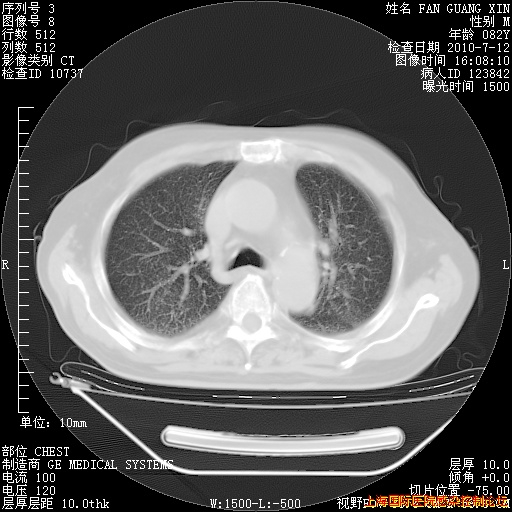

补发6月12日肺部CT肺窗

6月12日肺窗